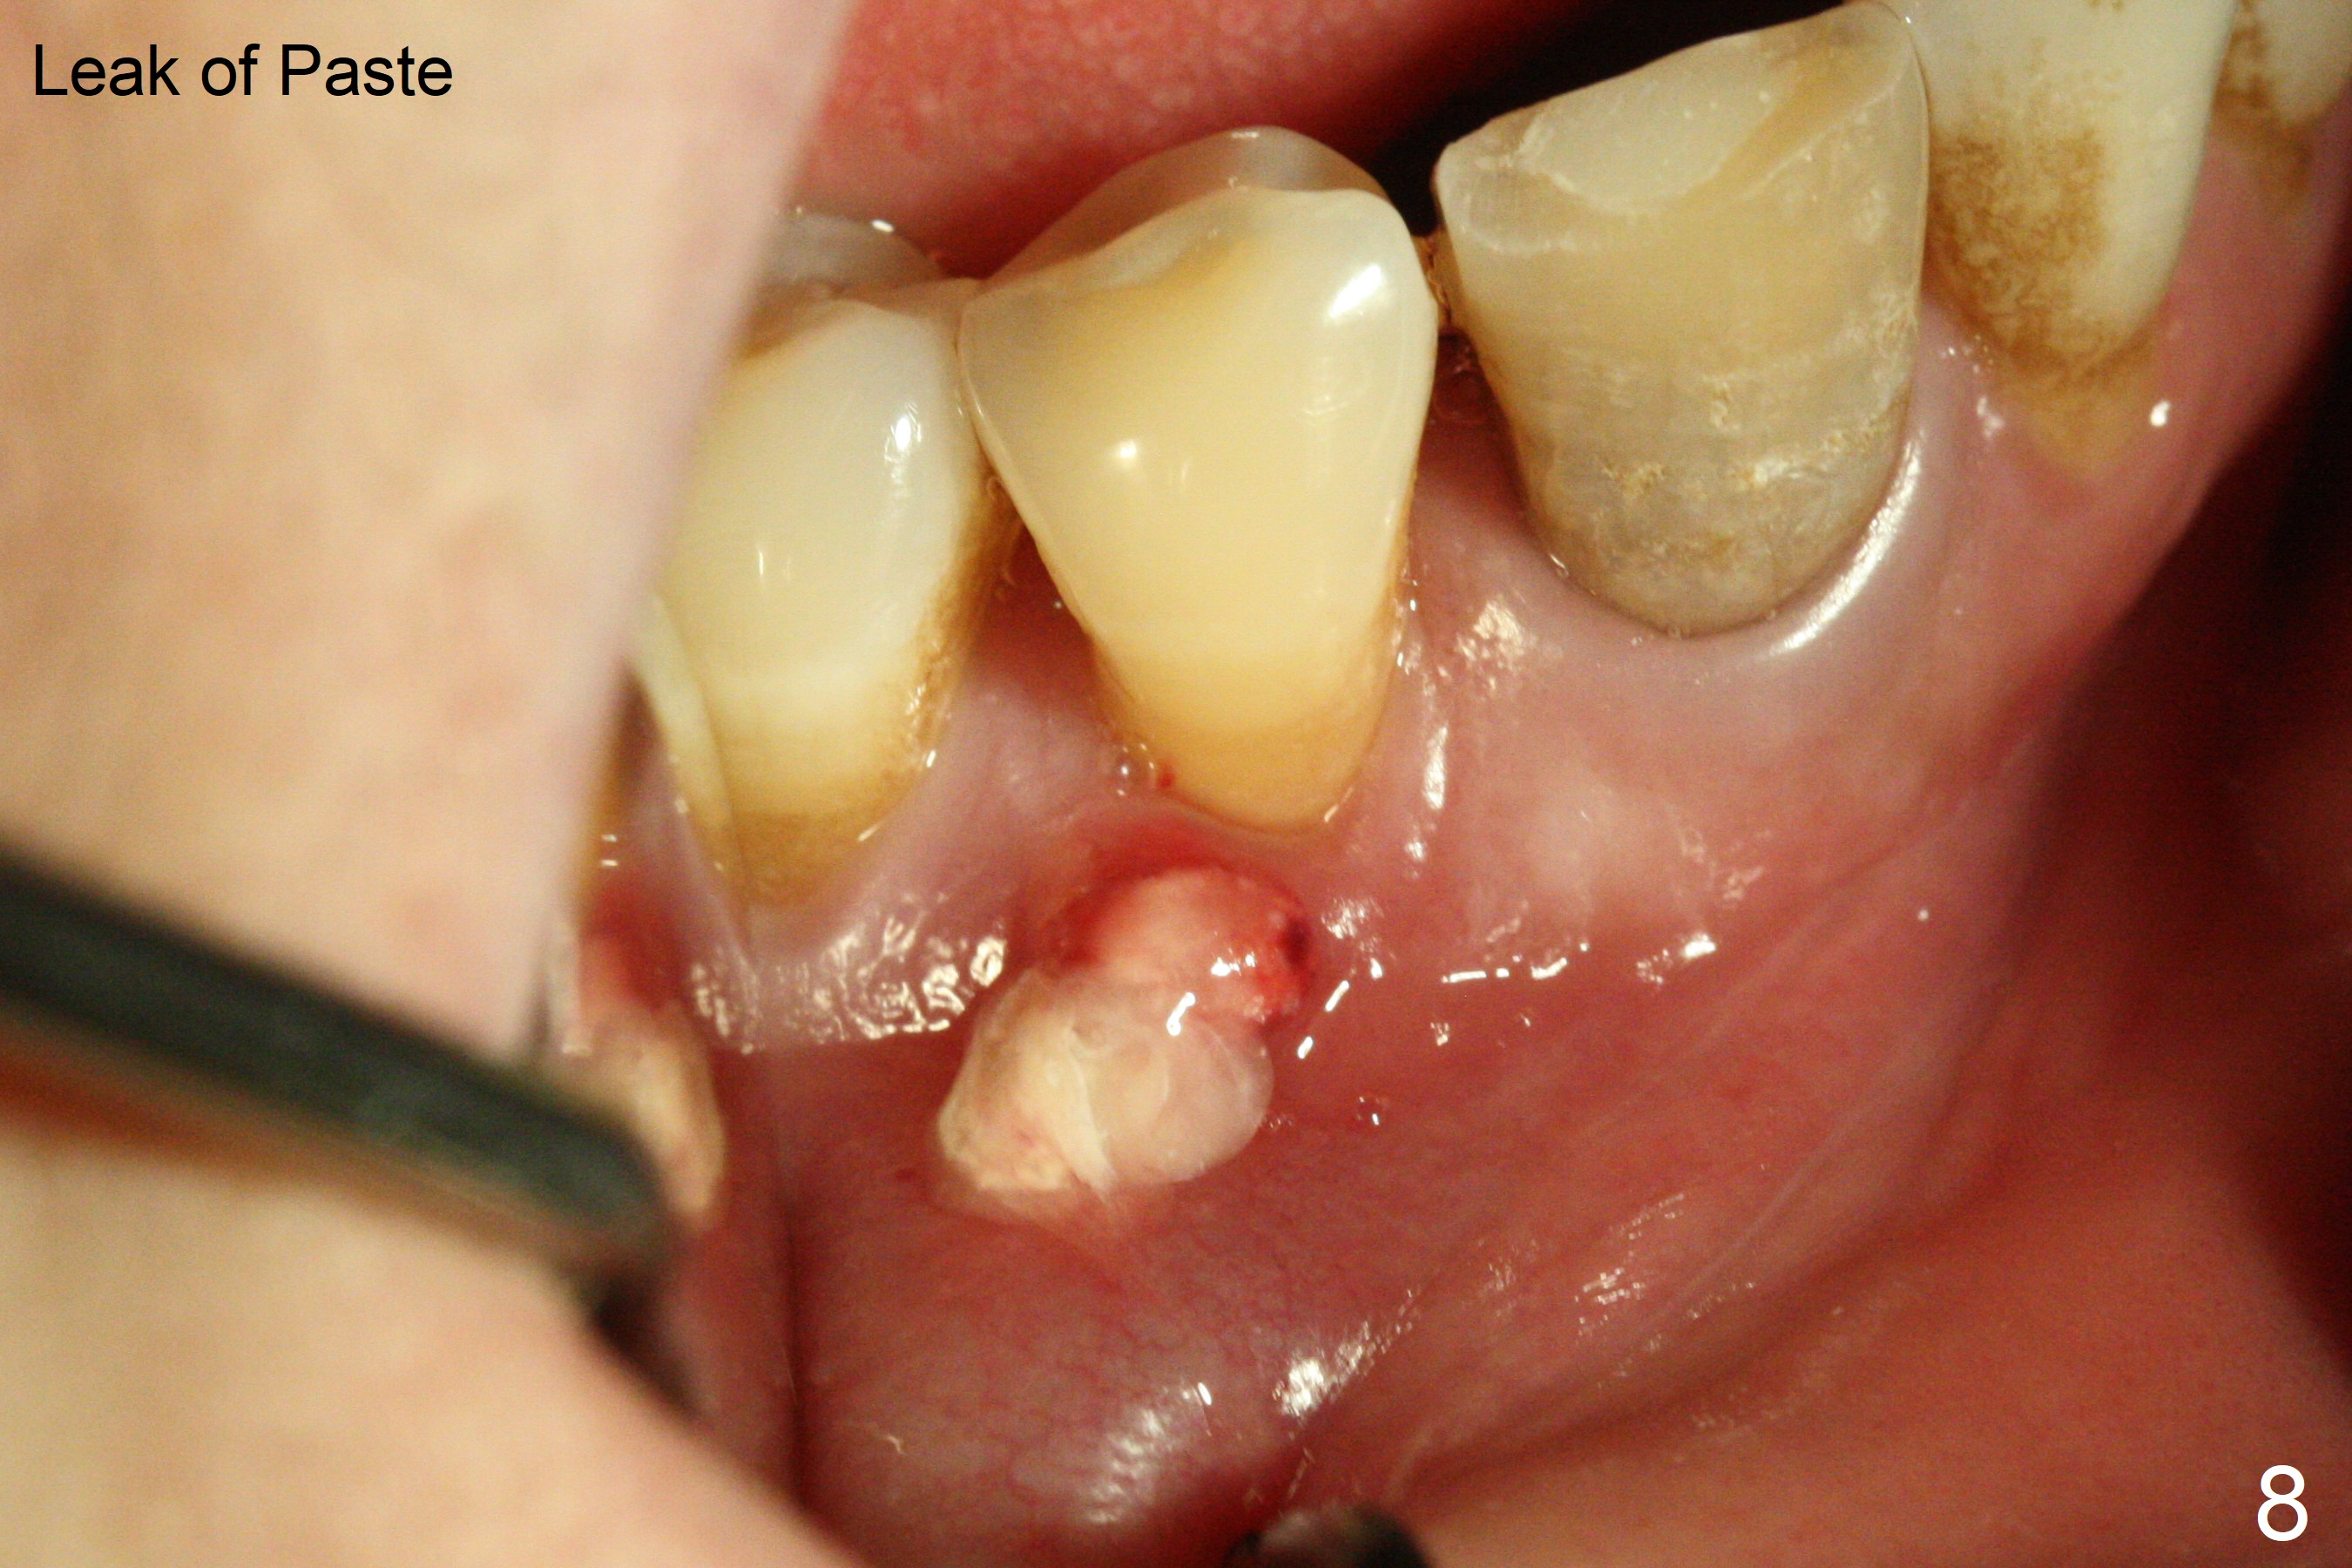

The patient reports that the fistula disappears after initial RCT at #27, but it seems to re-appear 1 month post canal debridement (Fig.5 >). After repeated debridement with #40 hand file at 23 mm, apply Endo Sequence BioCeramic Sealer and insert GT 40/.08 master cone with black carrier (Fig.6). One hour later, the patient returns with re-appearance of the fistula (Fig.7). Following local anesthesia, poking the fistula leads to sealer escape (Fig.8). After debridement of the fistula until the bone, PA is retaken (Fig.9). A crown was made in China; mesial radiolucency starts (Fig.10). The tooth remains asymptomatic 1 year 5 months postop (Fig.11). There is a lingual fistula with enlarged mesial radiolucency 2 years 3 months postop (Fig.12-14).